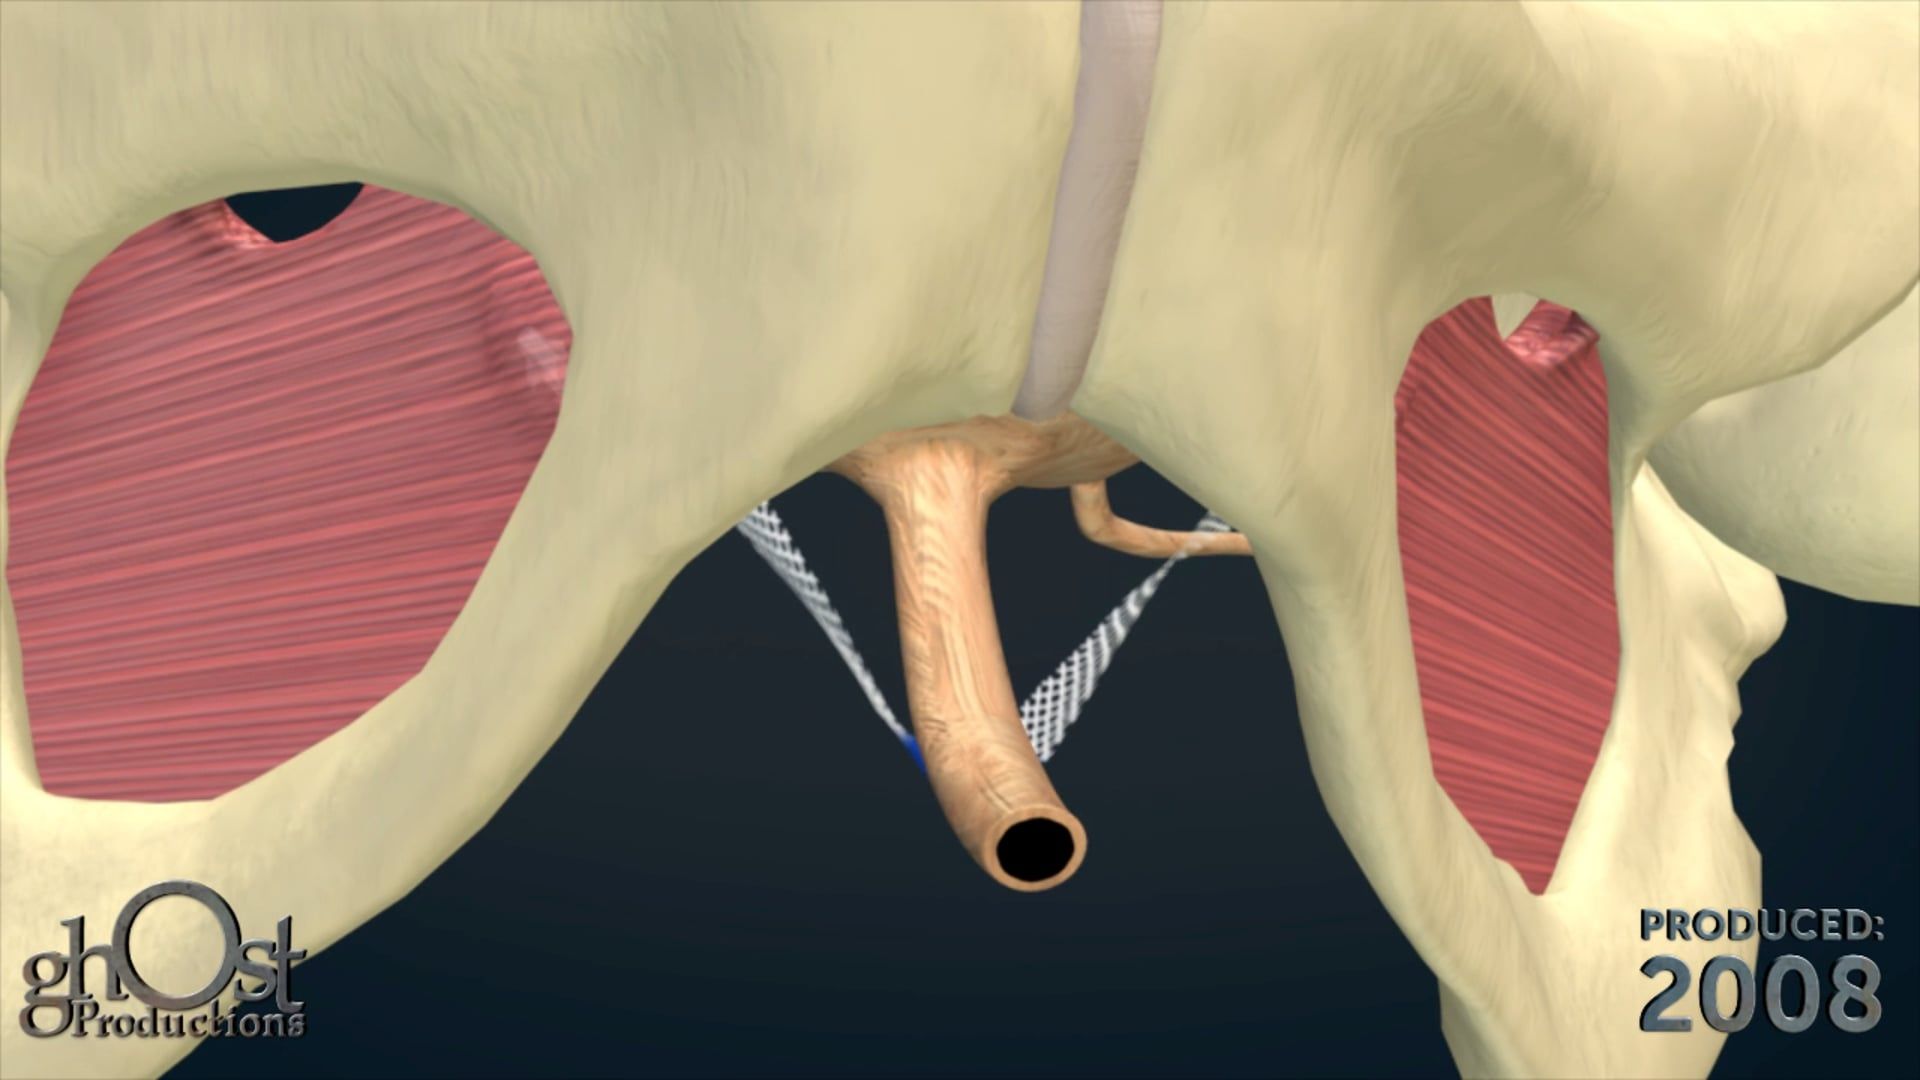

AMS partnered with Ghost Productions, a medical animation and graphics company, to create a series of animations and medical graphics that effectively communicated the benefits of their products. Ghost Productions worked closely with AMS's team to understand the mechanism of action of each product and create a visual representation of the process.

the animations and medical graphics produced by Ghost Productions proved to be instrumental in helping AMS effectively communicate the benefits of their products to their target audience. The visual aids helped potential customers and physicians understand the mechanism of action of each product and the benefits of using them to treat urological and gynecological conditions.